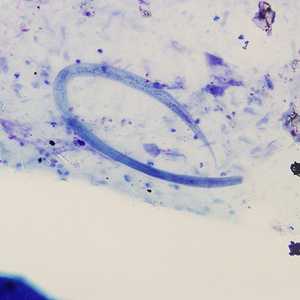

February - 2008 - Case #221

A survey was conducted to determine the prevalence of geohelminth infections in school-age children living in Haiti. The laboratory aspect of the survey consisted of processing stool specimens which were collected in 10% formalin.